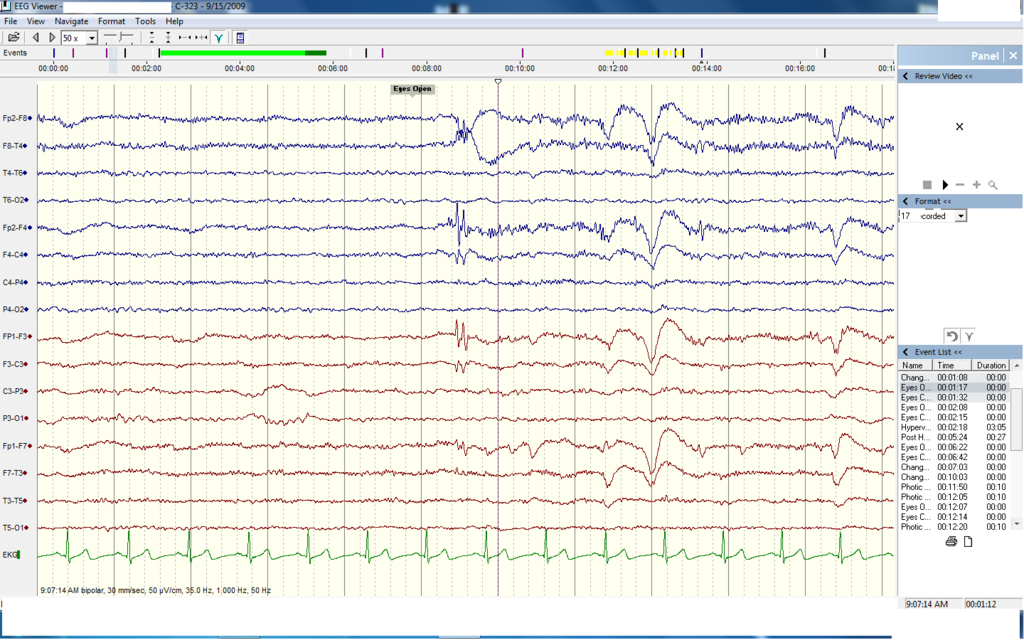

Last week I described how doctors use brain wave detection and reflex tests to determine which patients are dead. Despite all the scientific evidence, it’s still hard to pull the plug. My cousin died while on life support and as someone who was in the huddle with my aunt and uncle, I know it’s hard to believe a medical test when you‘re looking at a person who is warm and seems to be sleeping, in spite of tubes and wires of life support.